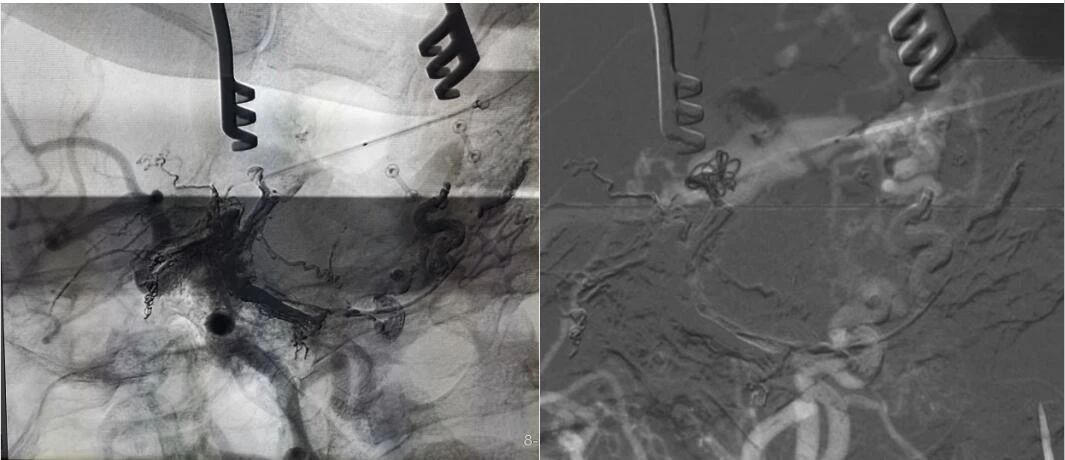

▲ 微导管造影确认后,注入 Onyx 18胶 5ml

经左侧股动脉以单弯造影管超选至左侧颈总动脉造影明确静脉穿刺点入路,予以穿刺针穿刺成功后造影明确在位,随后 Echelon 10微导管到位横窦,填入一枚弹簧圈做塞子,造影明确位置后,缓慢注入 Onxy18胶 5毫升,铸胶弥散良好,通过静脉逆向弥散至部分供血动脉内。复查造影,见瘘口完全被栓塞,引流静脉消失,手术成功。

▲ 术后影像